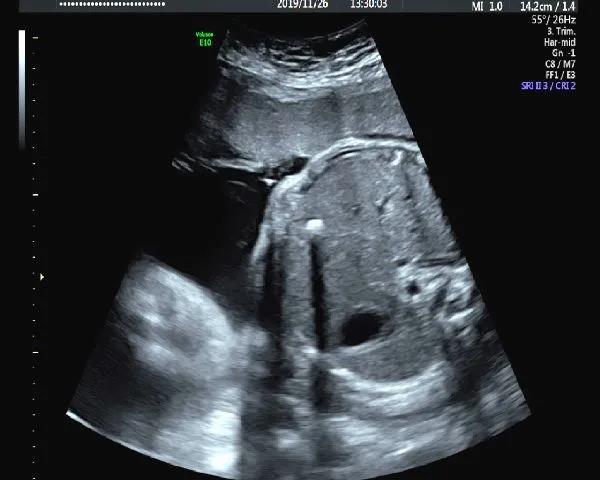

1.心脏强回声

心室强光点是孕期最为常见的强回声,这些孤立的强回声不会影响心功能,也不是胎儿心脏的结构异常的表现,一般孕晚期会消失,有时会追溯到新生儿期。其在正常胎儿中发生率在2%-5%。

宝妈们遇到这样的报告,如果染色体异常筛查低风险,我们可以选择乐观一些。但对本身存在染色体异常高风险的人群还是要更谨慎一些,要听听产科医生的意见。